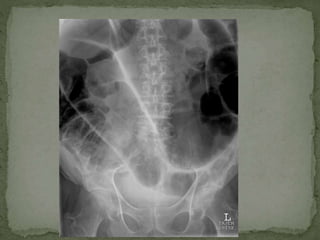

 CXR CHEST/ ABDOMIN

 Simple Investigations: Bloods tests (FBC, U&E, LFT, amylase, clotting, CRP, G&S/ ABG)  Urine dipstick  Pregnancy test (all women of child bearing age with lower abdominal pain)  CXR CHEST/ ABDOMIN  ECG  More ADVANCE investigations:  Contrast studies  Endoscopy (OGD/colonoscopy/ERCP)  CT  MRI